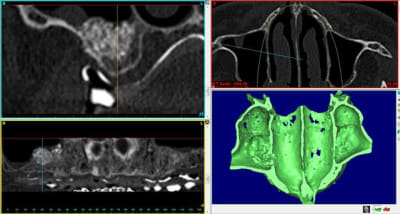

voici 4 scanners montrant la différence de résultat obtenu après un sinus lift.

3 droite : après

4 gauche : après

notez surtout qu'à gauche et à droite la consistance est vraiment différente.

à droite : BIO-OS

- grosses particules

- beaucoup de publications

- bouillies infâme lors de l'ouverture

- pas de résorption

- beaucoup de particules encapsulées

- c'est pas de l'os

- lutte contre la pneumatisation sinusienne

à gauche :GEN-OS

- pas de particules

- ressemble d'avantage à de l'os

- pas de sensation de bouillie

- semble plus homogène

- résorbable

- pas d'effet barrière contre la pneumatisation du sinus

- taux de résorption inconnu